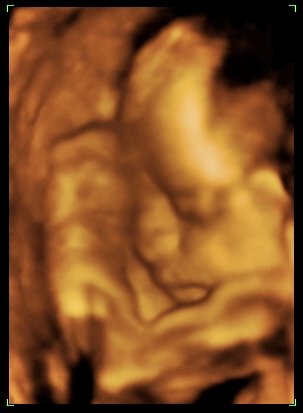

Előzmény az volt, hogy a dokimnál voltam pénteken, és megállapította, hogy Julcsika nem akkora, mint amekkorának lennie kellene (kisebb kb. egy héttel). Ezt ő a diétám számlájára írta, pedig mondtam neki, hogy nem eszem keveset, csak rengeteget megyek Beni miatt. Mindenesetre azt mondta, hogy függesszem fel a diétát, és két hét múlva újra UH... Persze hozzátette, hogy nem gondolja, hogy bármi gond lenne, mert a lepény 0 fokban érett, megfelelő mennyiségű a magzatvíz és semmi más jel nincs, de azért biztos, ami biztos.

Na, ma elmentünk a Genesis-be, ahol nagyon kedvesek voltak. A Lengyel Györgyné volt a szonográfus, és mivel Julcsika egész idő alatt aludt (!!! pedig amúgy állandóan izeg-mozog...), jól meg kellett dolgoznia, hogy egyáltalán a méreteit meg tudja nézni. Majdnem 50 percig voltam benn! Tényleg nagyon alapos nő, és nagyon kedves is, sajnálom, hogy már első alkalommal is nem hozzá mentünk.

Ő is kisebbnek mérte kb. 6 nappal, de amúgy minden rendben van. (Lehet, hogy mégis decemberi lesz a kishölgy?! :D )

Egyelőre farfekvéses, remélem, még befordul majd, mert császár után farfekvéssel a doki biztos nem fog nekimenni normál szülésnek...